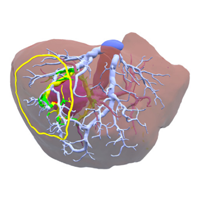

Virtual Resection

A collaborative virtual reality environment for liver surgery planning (2021)

Virtual resection with a deformable cutting plane (2004)

Impact of virtual tumor resection and computer-assisted risk analysis on operation planning and intraoperative strategy in major hepatic resection (2005)

Virtual reality applied to hepatic surgery simulation: the next revolution (1998)

Venous reconstruction based on virtual liver resection to avoid congestion in the liver remnant (2011)

Preoperative hepatic 3D models: virtual liver resection using three-dimensional imaging technique (2005)

Virtual liver resection and volumetric analysis of the future liver remnant using open source image processing software (2010)

Virtual hepatic resection using three-dimensional reconstruction of helical computed tomography angioportograms (2001)